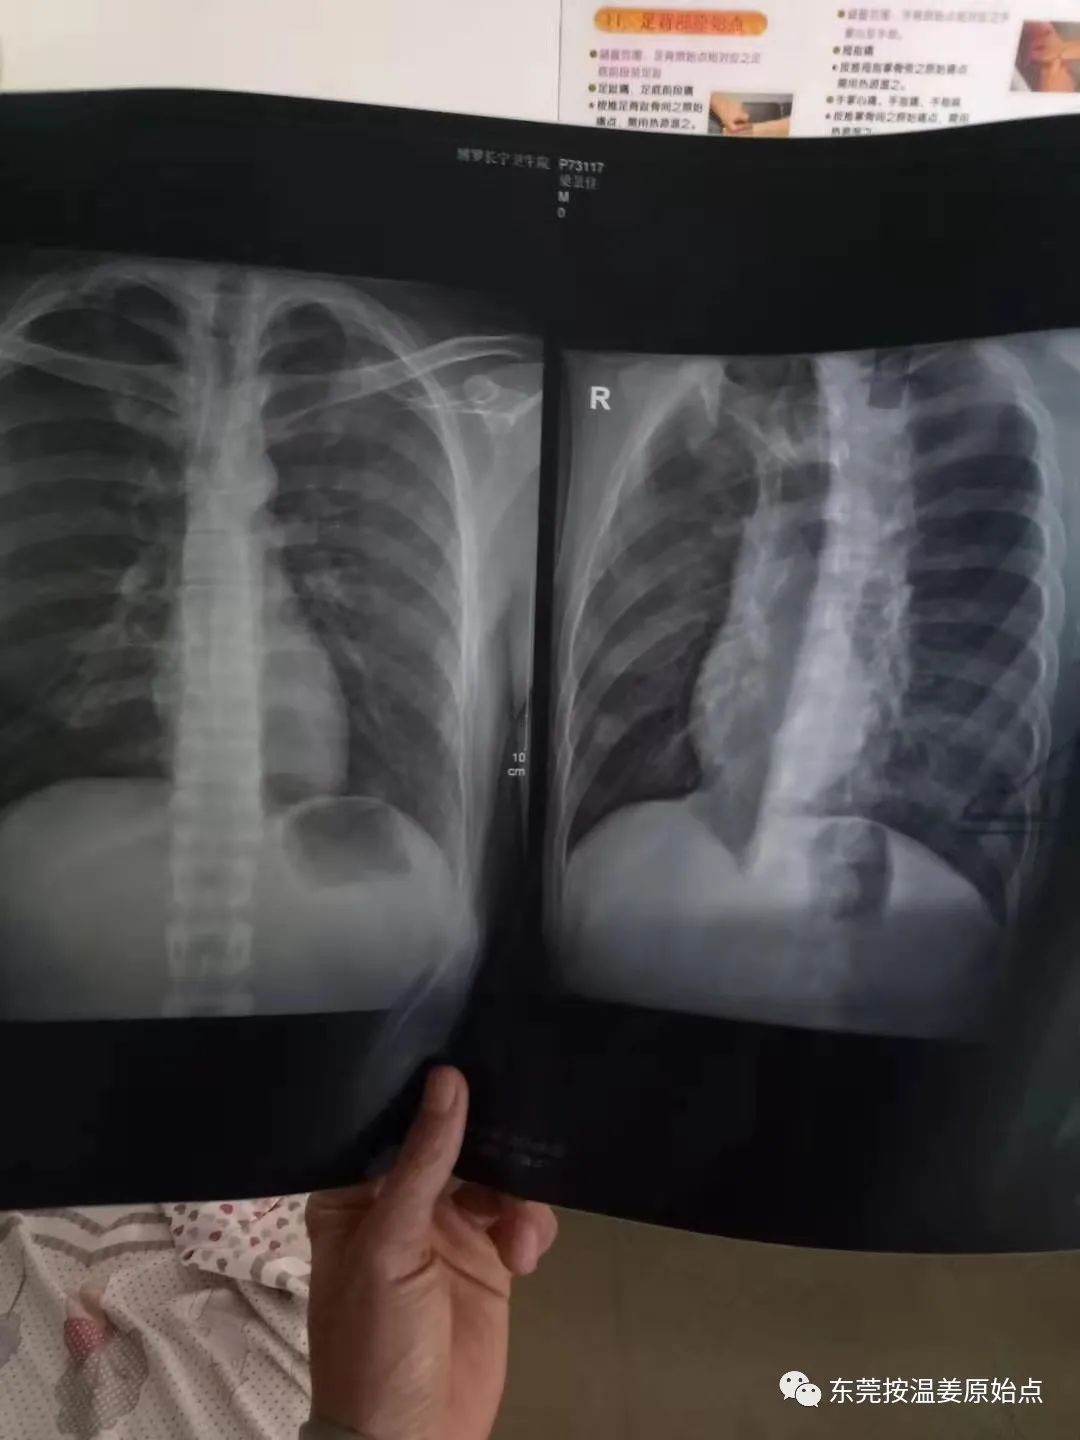

在罗浮山的长宁医院头部照了CT:左侧上颌窦几处前壁骨折丶凹陷。照胸X光:左侧肩胛骨下角骨折,可见骨皮质翘起。医院说伤情严重需要住院一个月,大概一天三千元治疗的费用,我要求马上强行出院,医生没办法,包扎了一下流血不止的头部伤口就出院了。